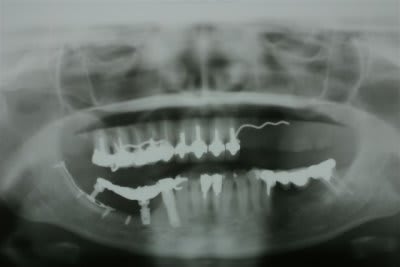

1 Radiographie panoramique avant implantation.

Les deux implants du haut ont été perdus.

2La greffe autologue prélevée à la hanche à totalement fondu.

Il ne reste que la vis d'ostéosynthèse qui avait servi à fixer le greffon.